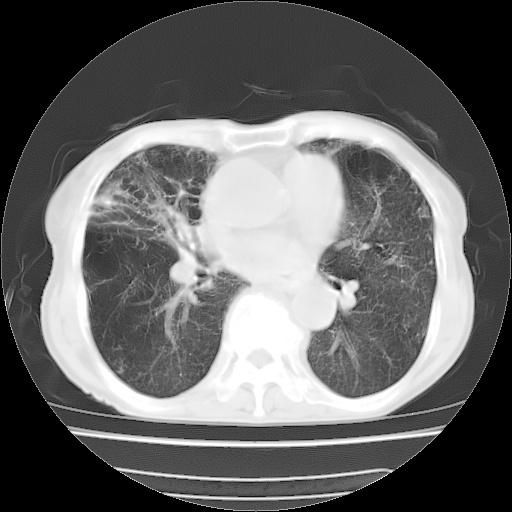

病人发热、气促就诊。原二周前已行ct扫描,当时诊断为双肺下叶、右肺中叶支气管扩张并感染,双肺上叶片状渗出性病变。今天复查胸部ct,双肺下叶支气管扩张并感染病灶较前明显吸收,但双肺上叶渗出性病变较范围较前明显增大。

现传今天ct图像给大家讨论。

双肺感染性病变,不排除机遇性肺炎。双下肺间质纤维化较明显。

双肺间质广泛纤维化,上叶炎症考虑特异性感染,例如念珠菌,克雷伯杆菌什么的,建议实验室检查。

双肺多发大片状、斑片状高密度渗出影,部分实变,考虑病毒性肺炎。